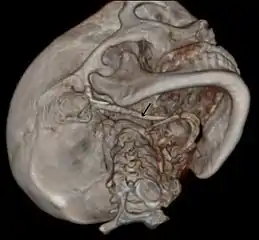

3D-reconstructed CT scan showing bilateral stylohyoid ligament ossification

Imaging is important and is diagnostic. Visualizing the styloid process on a CT scan with 3D reconstruction is the suggested imaging technique.[12] The enlarged styloid may be visible on an orthopantogram or a lateral soft tissue X ray of the neck.